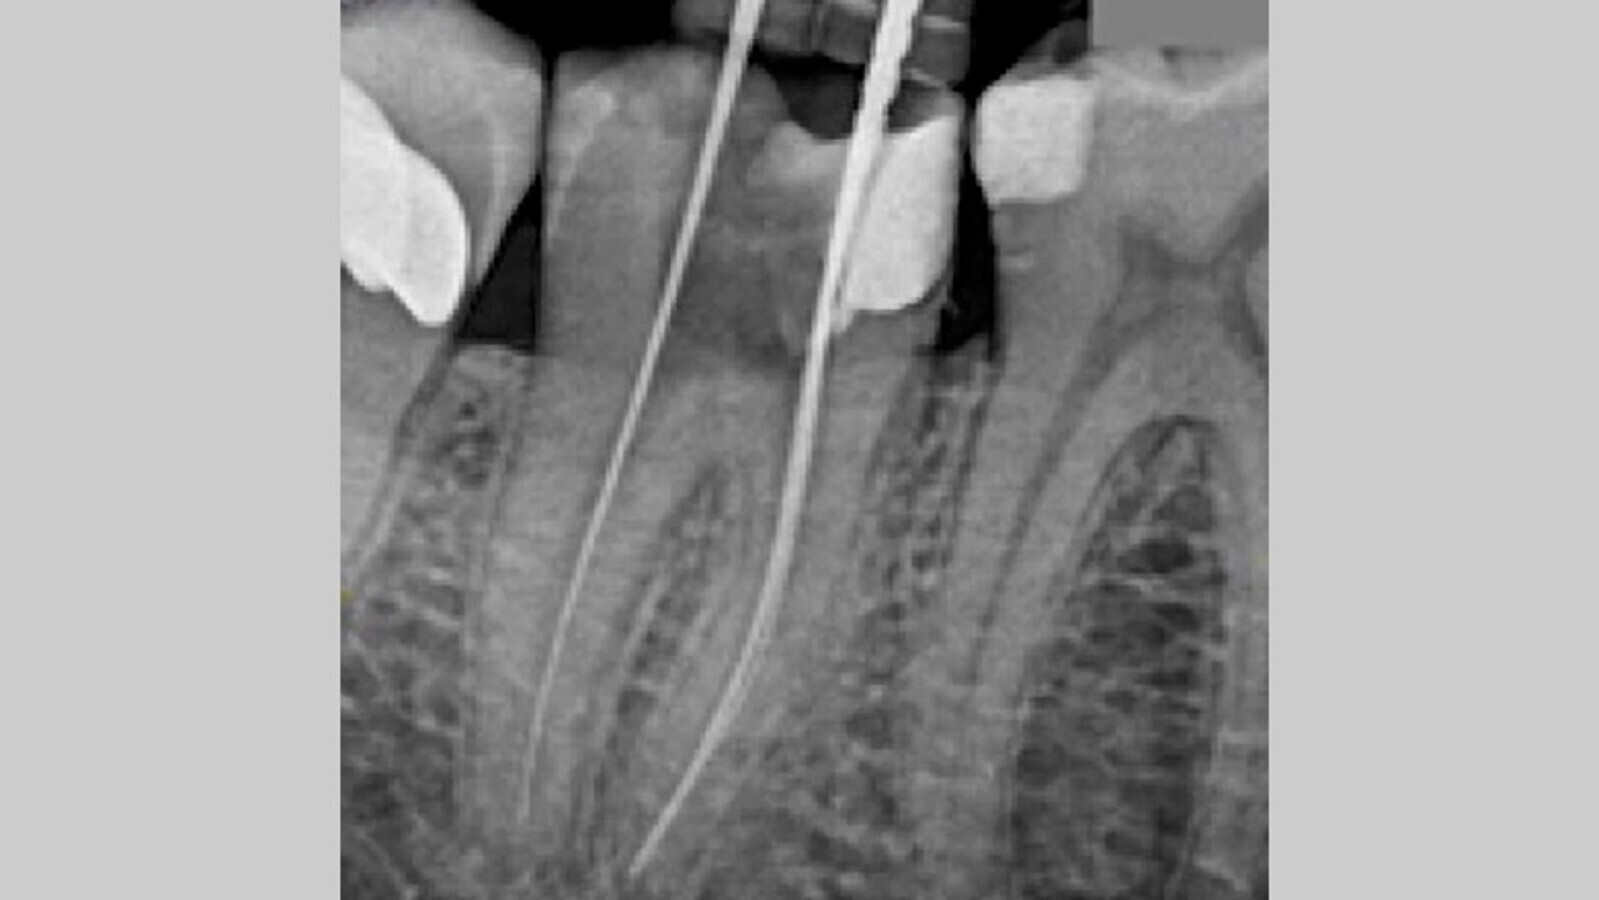

La configuración de los conductos mesiales resulta en la unión en el tercio apical, compartiendo el mismo foramen. Una vez se permeabilizan los conductos con la lima del 10 K- files, se realiza un glide path hasta alcanzar con una lima 15 k file (Denstply) la longitud de trabajo. Es en ese momento se toma una radiografía de comprobación de la longitud de trabajo actual (Fig. 3), y tras confirmar que la longitud es correcta, procedemos a realizar la instrumentación mecánica, en este caso reciprocante con el sistema Reciproc Blue (VDW Dental) que consta de varias limas reciprocantes para la limpieza y conformación de los conductos. Utilizamos este sistema en el motor Endoradar (Woodpecker) el cual viene equipado con localizador electrónico de ápices incorporado. Para la conformación final de los conductos a nivel apical se utiliza el sistema ProFile (Denstply), concretamente la lima ProFile 35.04 en conductos mesiales y la lima 40.04 en el conducto distal. Durante toda la instrumentación irrigamos con NaOCl al 4,25%. Realizamos el protocolo final de activación con activador sónico, tres ciclos: NaOCl 4,25% - EDTA 17% - NaOCl 4,25%. Secamos los conductos con puntas de papel calibradas a los calibres finales de cada conducto (Denstply).

Fig. 3. Radiografía de conductometría. Localización de dos conductos mesiales y un conducto distal.